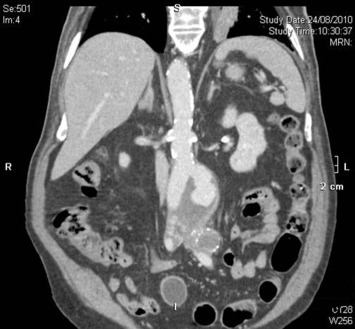

The ruptured group presented survival rates of 53.5%, 50.5%, 47.5%, 42.3%, 38.0%, 21.9%, and 12.5% at 1 year, 2 years, 3 years, 4 years, 5 years, 10 years, and 15 years, respectively; while the nonruptured group had survival rates of 91.5%, 88.0%, 83.7%, 78.3%, 73.0%, 43.0%, and 25.3% (log rank p < 0.001; Fig. 2). For those who died 30 days after their operation, only six patients died from aneurysm related causes, giving a late aneurysm-related mortality of 1.8% (Table 5). There were a total of three (0.9%) patients who underwent late re-interventions due to graft related events. The first patient underwent open repair in 1994 at the age of 66 years. The 4.4 cm infrarenal aortic aneurysm and 5.7 cm left iliac aneurysm were replaced with aorto-bi-iliac knitted Dacron graft. He presented with recurrent gastrointestinal bleeding of unknown origin 6 years later. Upper endoscopy and colonoscopy failed to localize the bleeding source. Laparotomy and enteroscopy showed suspicious bleeding from the proximal jejunum and possible graft-to-jejunum fistula. Bleeding was settled with aorto-uni-iliac endovascular stenting and cross femoral bypass. The patient is still alive to date (Fig. 3). The second patient underwent open repair with aorto-bi-femoral woven Dacron graft in 1993 at the age of 72 years. Seven years later, he was incidentally found to have a pulsatile mass at the epigastrium with a CT scan showing an infrarenal 8 cm proximal anastomosis pseudoaneurysm. Treatment was standard endovascular repair (Fig. 4). The last patient had open repair surgery with aorto-bi-iliac woven Dacron graft in 1993 at the age of 76 years. He complained of epigastric pain 20 years later with a CT scan showing a 9 cm proximal perivisceral pseudoaneurysm, which was settled with endovascular stenting with fenestration to all four visceral vessels (Fig. 5; Table 6). In addition, 17 (5.0%) patients developed thoracic or iliac aneurysms in later life. They were treated with open or endovascular repair (Table 7).

Late intervention Patient 2.

Fig. 4.